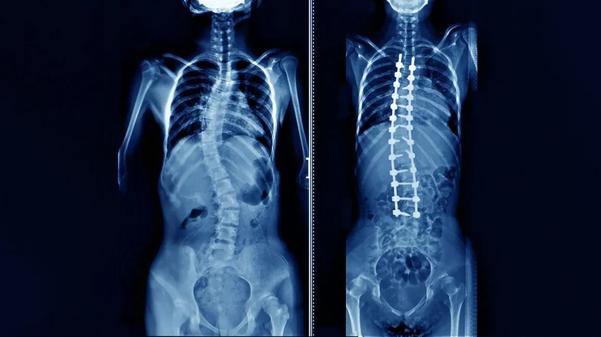

Scoliosis Surgery in Nashik for Spine Realignment ...